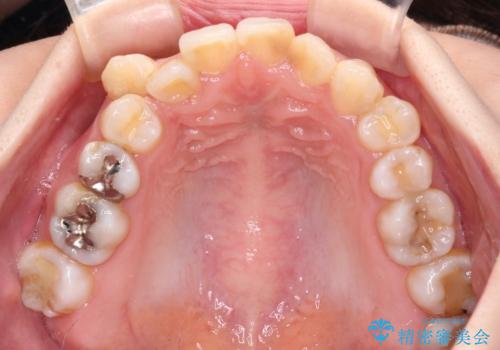

- 上下の八重歯と前歯のデコボコを気にして来院された患者様です。

右上と左下の八重歯が特に著しく、上顎正中が右側にシフトしていました。

デコボコが強いため小臼歯4本を抜歯し、上顎正中を左側に移動させるために補助装置を使用して、ワイヤー装置にて矯正治療を行うこととしました。